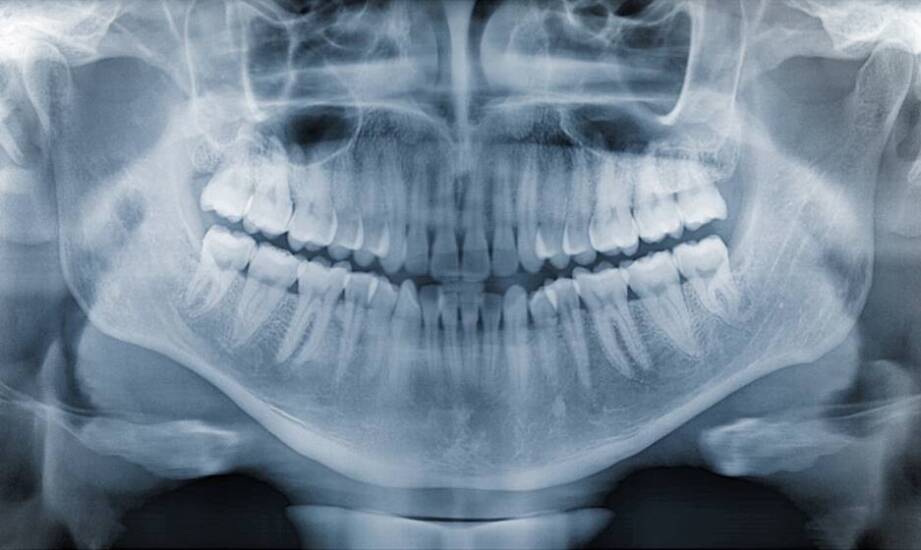

RTG zębów to narzędzie w diagnostyce stomatologicznej, które pozwala na zobrazowanie struktury zębów oraz otaczających tkanek. Dzięki tej technologii specjaliści mogą zidentyfikować problemy, które mogą być niewidoczne podczas standardowego badania. Gabinet Dentystyczny Katarzyny Mech-Makówki, oferujący usługi RTG zębów, prowadzi obsługę pacjentów zgodnie z obowiązującymi standardami. W artykule omówimy, jak RTG wpływa na proces diagnozowania oraz jakie aspekty są związane z jego wykorzystaniem. Wykorzystanie RTG zębów dotyczy oceny stanu uzębienia i tkanek jamy ustnej, co ma znaczenie dla zdrowia jamy ustnej mieszkańców Zgierza.

RTG zębów w Zgierzu i innych miejscowościach ma na celu wykrywanie próchnicy, jednego z istotnych problemów stomatologicznych. Obrazowanie radiologiczne umożliwia identyfikację wczesnych zmian próchnicowych, które mogą być trudne do zauważenia gołym okiem. W takich sytuacjach dentyści mogą podejmować działania diagnostyczne i terapeutyczne, zanim problem się pogłębi. Wczesne wykrycie próchnicy jest szczególnie istotne w przypadku dzieci, u których mleczne uzębienie jest bardziej podatne na uszkodzenia. Regularne wykonywanie rtg zębów w Zgierzu pozwala monitorować stan uzębienia oraz kontrolować rozwój ewentualnych zmian próchnicowych. RTG zębów w Zgierzu realizowane jest przez personel medyczny przy użyciu aparatury spełniającej wymagane normy, co ma na celu zachowanie bezpieczeństwa pacjentów. Ponadto obrazowanie radiologiczne to stosunkowo krótki i zazwyczaj dobrze tolerowany zabieg, który nie wymaga specjalnego przygotowania ze strony pacjenta. W ten sposób dentyści mogą rozpoznawać problemy stomatologiczne oraz prowadzić dalsze postępowanie lecznicze zgodnie z aktualną wiedzą medyczną.

RTG zębów jest stosowane w ocenie stanu tkanek okołozębowych oraz korzeni. Dzięki uzyskanym obrazom dentyści mogą rozpoznawać problemy takie jak zapalenie dziąseł czy choroby przyzębia. To ma na celu planowanie leczenia i monitorowanie postępów terapii. W przypadku zapalenia dziąseł RTG zębów pomaga ocenić głębokość kieszonek oraz stan kości wyrostka zębodo łowego. Na tej podstawie lekarz może zdecydować o metodzie leczenia, czy to będzie terapia zachowawcza, czy też zabiegi chirurgiczne. W sytuacji chorób przyzębia, takich jak przewlekłe zapalenie, RTG zębów umożliwia ocenę stopnia zaawansowania schorzenia oraz planowanie dalszych działań terapeutycznych. Obrazowanie radiologiczne jest także pomocne w diagnostyce problemów związanych z korzeniami, takich jak torbiele czy zmiany nowotworowe. W takich przypadkach dentyści mogą podjąć odpowiednie kroki w celu dalszej diagnostyki i leczenia, zgodnie z obowiązującymi wytycznymi. Regularne wykonywanie zdjęć rentgenowskich dotyczy wczesnego wykrywania nieprawidłowości oraz podejmowania działań zapobiegawczych, co ma znaczenie dla zdrowia jamy ustnej pacjentów w Zgierzu.